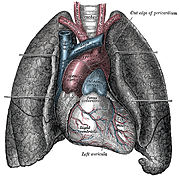

Anatomy (from the Greek ἀνατομία anatomia, from ἀνατέμνειν ana: separate, apart from, and temnein, to cut up, cut open) is a branch of biology that is the consideration of the structure of living things. It is a general term that includes human anatomy, animal anatomy (zootomy) and plant anatomy (phytotomy). In some of its facets anatomy is closely related to embryology, comparative anatomy and comparative embryology, through common roots in evolution.

Anatomy is subdivided into gross anatomy (or macroscopic anatomy) and microscopic anatomy. Gross anatomy (also called topographical anatomy, regional anatomy, or anthropotomy) is the study of anatomical structures that can be seen by unaided vision. Microscopic anatomy is the study of minute anatomical structures assisted with microscopes, which includes histology (the study of the organisation of tissues), and cytology (the study of cells).

Human anatomy, including gross human anatomy and histology, is primarily the scientific study of the morphology of the adult human body.